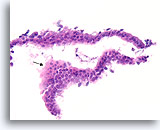

PAPILLOOM

Papilloom, Borst FNA, Celblok.

Deze afbeelding van dezelfde FNA als in afbeelding 18 bevat een duidelijk papillaire architectuur.

10X

Papilloom, Borst FNA, Celblok.

Deze afbeelding van dezelfde FNA als in afbeelding 18 bevat een duidelijk papillaire architectuur.

10X